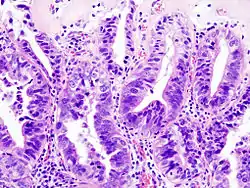

- Gallbladder adenocarcinoma lymphatic invasion histopathology

- Gallbladder adenocarcinoma histopathology